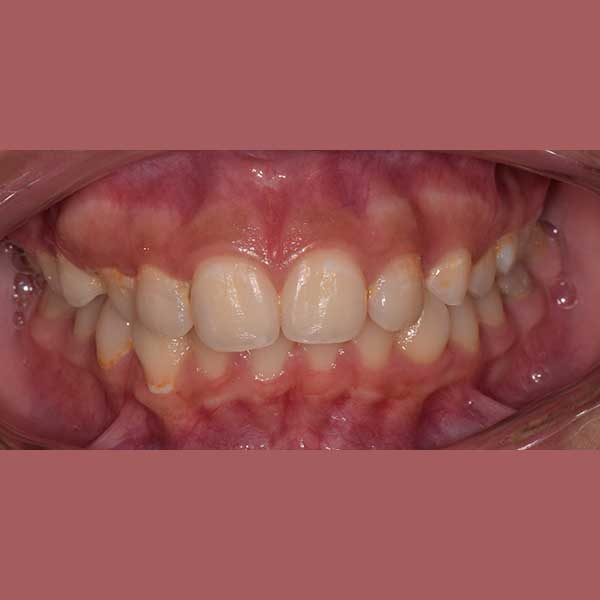

AFTER

At the end of the treatment she got back her beautiful smile and to get her confident smile again!